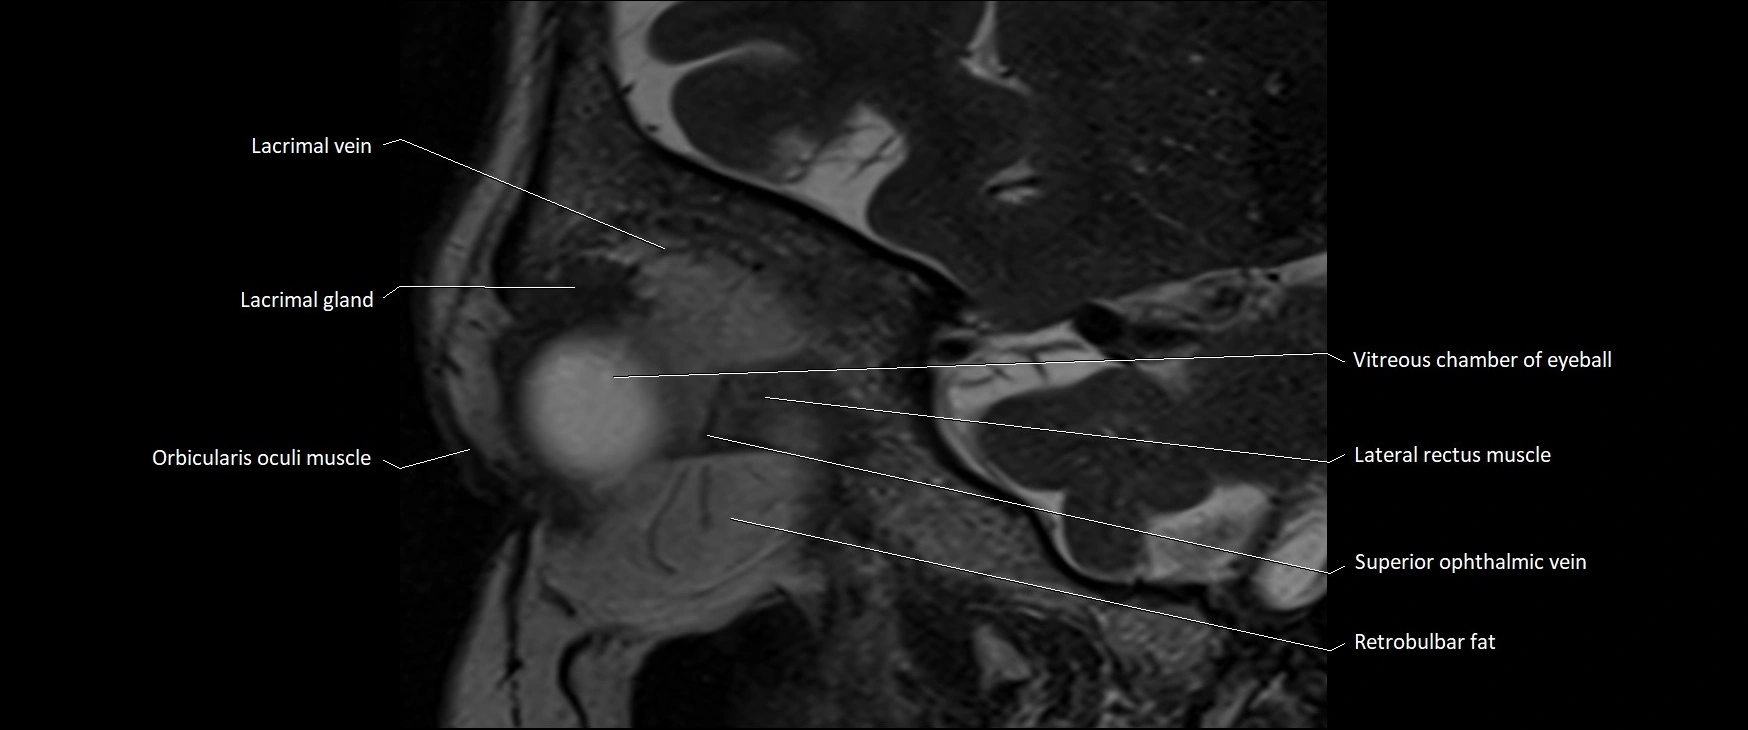

- Lacrimal gland

- Lacrimal vein

- Lateral rectus muscle

- Orbicularis oculi muscle

- Retrobulbar fat

- Superior ophthalmic vein

- Vitreous chamber of eyeball